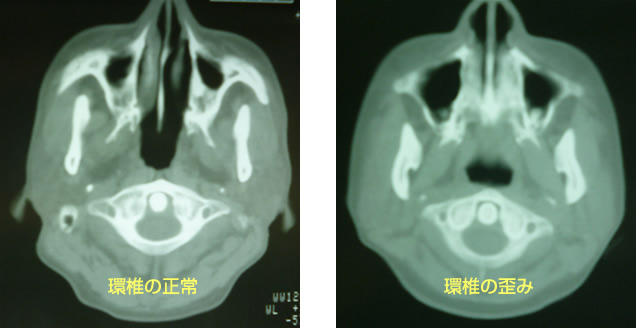

頸部に回旋する時に起こる上部頸椎と後頭骨に痛みを感じ又、同側の舌の半分がしびれ舌の違和感を感じたり頭痛の原因にもなります。急に頸椎を回旋すると頸椎2番目が環軸関節上でけん引され大後頭神経、小後頭神経に影響を与え、頭痛、舌の違和感の原因にもなるといわれています。私の調査研究では軽い環軸関節(後頭骨と第一頸椎)の歪みは多数の患者さんに見受けられました。又、歪みは椎骨動脈の歪みにもなり血流の変化に関与します。

又、頸部交感神経に影響を与え頭痛、目、鼻、喉頭、耳まで様々な症状を呈するのではないかと思われます。